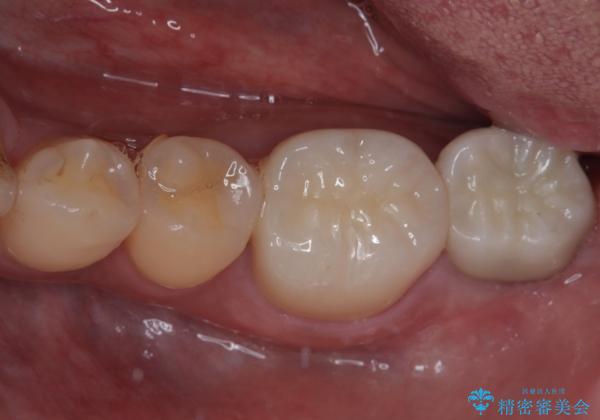

特に症状はなく、神経組織も健全な状態であったため、むし歯を全て取り切った後にフルジルコニアクラウンにて補綴することとしました。

銀歯などを使用する保険診療は、歯との境界の適合が悪く、むし歯の再発リスクが高いため、長期的な観点から使用は推奨されません。